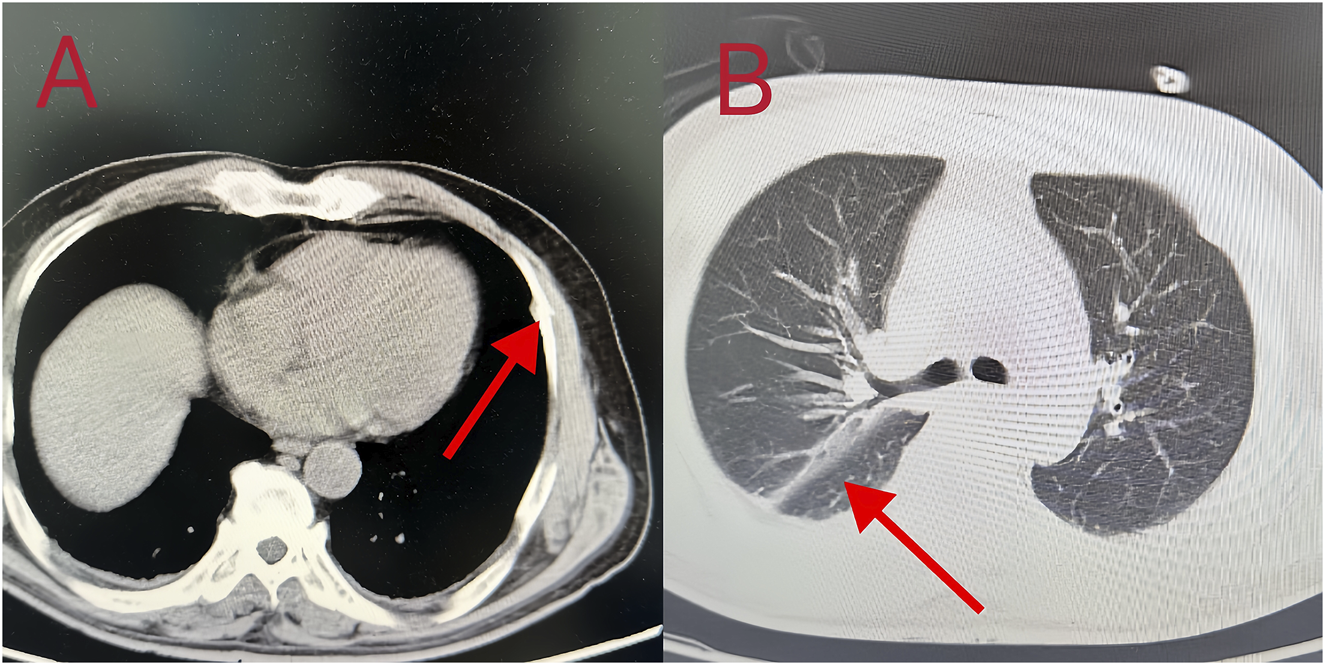

Patient 8 was a 53-year-old man who ingested 10 g of compound schizonepeta fumigation lotion on 4 February 2024, and was admitted to a local hospital. An electrocardiogram conducted at the local hospital revealed ventricular tachycardia and premature ventricular contractions (Figure 2D). After admission, he continued to experience malignant arrhythmias and unstable circulation. He received extracorporeal membrane oxygenation supportive treatment for 4 days, tracheal intubation and assisted ventilation for 8 days, hemofiltration five times, and hemoperfusion five times. For further diagnosis and treatment, he was transferred to our hospital on 16 February 2024. Physical examination on admission (at our hospital) revealed a body temperature of 38.5°C, heart rate of 92 beats/min, respiration rate of 16 breaths/min, blood pressure of 135/82 mmHg, an impaired mental state, and an inability to communicate. The electrocardiogram upon admission revealed a sinus rhythm and non-specific T-wave abnormalities. Laboratory test results were as follows: white blood cell count, 16.50 × 109/L (3.5–9.5 × 109/L); neutrophil ratio, 77.50% (40%–75%); alanine aminotransferase, 61 IU/L (9–50 U/L); creatine kinase, 649 IU/L (55–170 IU/L); and creatine kinase isoenzyme, 4.30 ng/mL (0.3–4 ng/mL). At the local hospital, measurement of aconitine, hypoaconitine, and mesoaconitine concentrations revealed blood levels of 205, 58, and 23 ng/mL, respectively. However, upon transfer to our hospital, these compounds were untraceable in the patient’s blood. The admission diagnosis was aconitine poisoning. The patient underwent electrocardiographic monitoring, organ protection, anti-infective treatment, fluid replacement, nutritional support, and other comprehensive treatments. On day 3 of admission, his white blood cell count was 22.50 × 109/L (3.5–9.5 × 109/L), neutrophil ratio was 87% (40%–75%), creatine kinase level was 182 IU/L (55–170 IU/L), and liver and kidney functions were normal. Chest computed tomography revealed slight inflammation in both lungs and a partial left rib fracture (Figures 3A, B). Brain magnetic resonance imaging revealed symmetrical abnormal signals in bilateral basal ganglia and bilateral parietal and temporal cortices, which was considered to be due to toxic encephalopathy based on his medical history (Figures 4A–C). Salvianolate (200 mg qd) was given to improve microcirculation symptomatic treatment. On day 7 of admission, white blood cell count, 12.98 × 109/L (3.5–9.5 × 109/L), the liver and kidney functions and myocardial enzymes were normal. After 18 days of treatment, the patient improved and was discharged. The patient was discharged for local rehabilitation. During the recent telephonic follow-up, the patient basically returned to normal but still had stuttering and a low voice tone. The family members will bring the patient to the hospital for reexamination in the near future.

Figure 3. (A, B) Chest CT images showed bilateral pneumonia, a small amount of bilateral pleural effusion, and partial rib bone discontinuity.